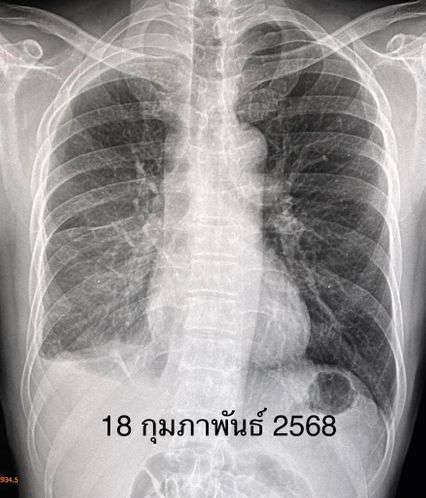

หลังเอาท่อระบายน้ำในปอดออกยังมีก้อนเลือดเกาะอยู่ในเยื่อหุ้มปอด แพทย์ส่งชิ้นเนื้อมะเร็งจากเยื่อหุ้มปอด ตรวจพบการกลายพันธุ์ของยีน T790M ที่ตำแหน่ง exon 20 แสดงว่า มะเร็งน่าจะตอบสนองต่อยา osimertinib จึงเริ่มให้ยา Tagrisso (osimertinib) 80 มก.กินวันละ 1 ครั้ง วันที่ 31 มกราคม 2568

หลังกินยา osimertinib 3 สัปดาห์ ผู้ป่วยดีขึ้น อาการเหนื่อยและปวดกระดูกลดลง เอกซเรย์ปอด พบก้อนเลือดในเยื่อหุ้มปอดหายไป น้ำในช่องเยื่อหุ้มปอดลดลง